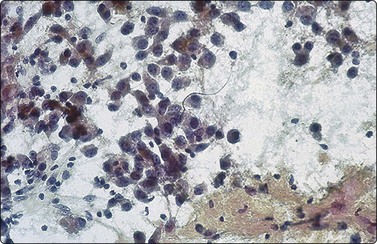

image

Fig. 17.7 Wilms’ tumor (nephroblastoma)

Aspirate smear demonstrating the epithelial component with glandular arrangements of primitive cells that are arranged in complex branching patterns (Diff-Quik ×400).